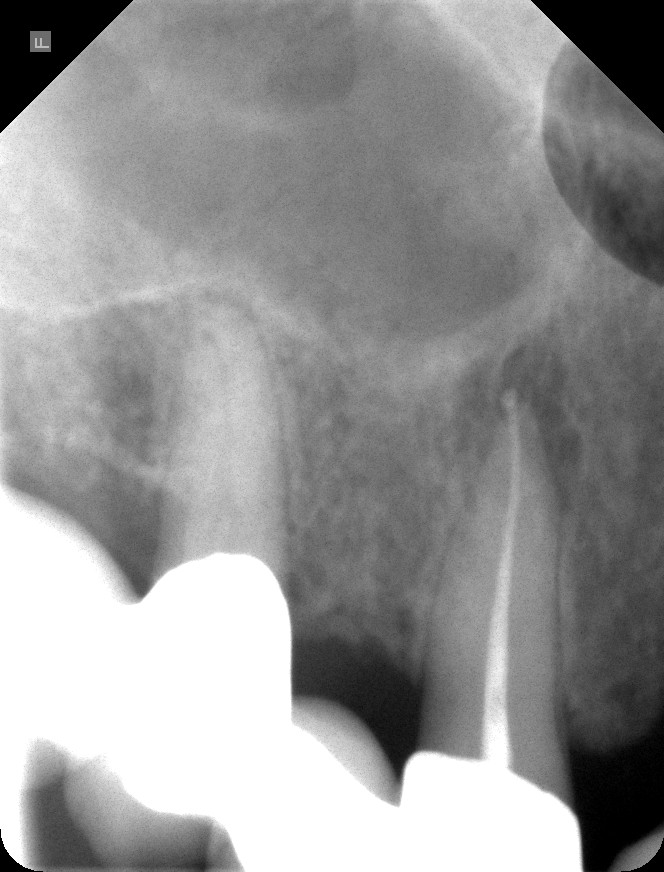

Wurzelkanalbehandlungen des Tages: Zähne 43 und 44

Der Patient ist 84 Jahre alt. Die Mundöffnung ist eingeschränkt, die Behandlung musste durch vorhandene Kronen hindurch und unter Kofferdam erfolgen.

Ausgangsröntgenbild:

Die Wurzelkanalfüllungen sind homogen und reichen bis zur Wurzelspitze (=Apex):

Die Zähne haben eine günstige Prognose.